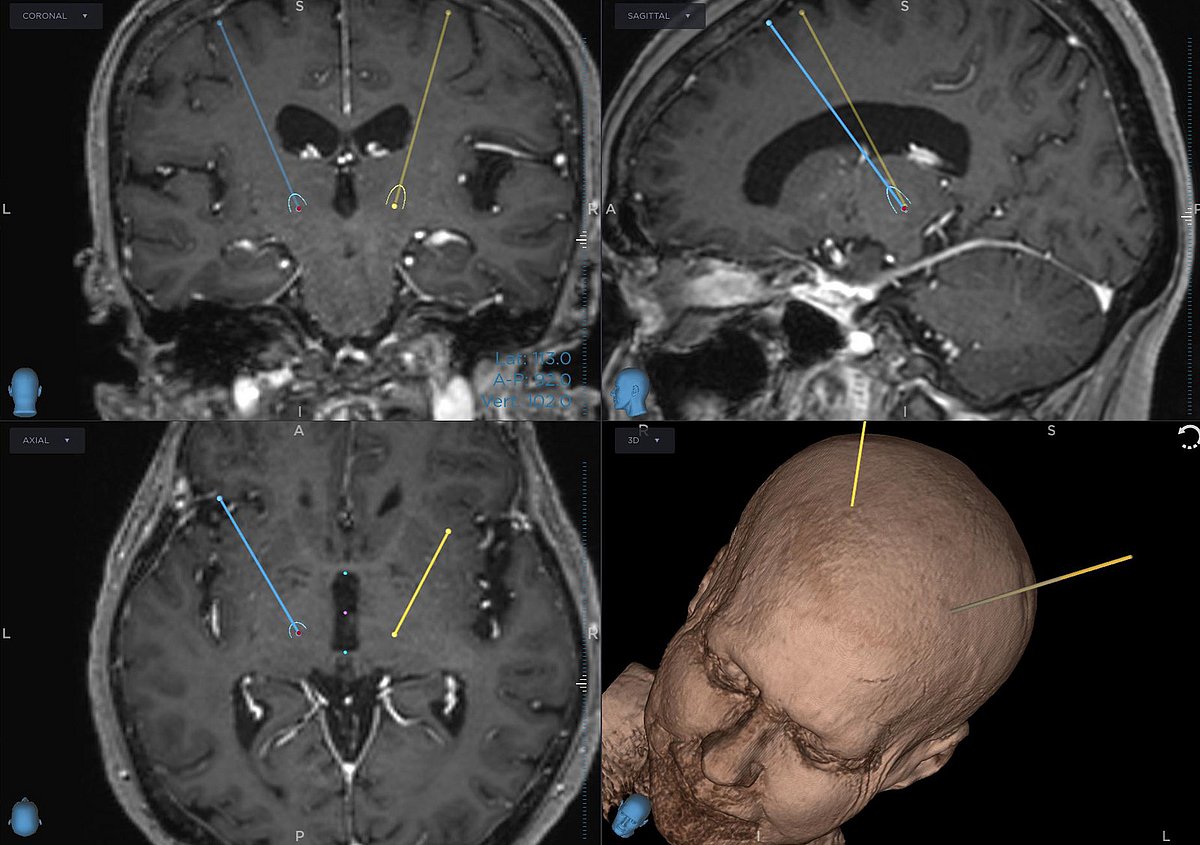

„Gerade bei Frauen wird die Erkrankung im Frühstadium oft verkannt oder auf die Psyche geschoben und daher nicht oder nicht richtig behandelt“, ordnet Dr. Schmidt ein. Nach mehr als dreißig Jahren hatte sich Irene F. beinahe mit ihrer Bewegungsstörung abgefunden. Doch als sie 2022 aufgrund eines anderen gesundheitlichen Problems in die Kreisklinik Roth kam, überwiesen die dortigen Ärztinnen und Ärzte sie zur Behandlung des Tremors an die Bewegungsambulanz der Molekular-Neurologischen Abteilung des Uniklinikums Erlangen. „Dort wurde mir das erste Mal wirklich geholfen!“, erinnert sich die 71-Jährige. Auch in Erlangen wurden zu Beginn medikamentöse Therapieversuche unternommen – vergeblich. Daher unterbreiteten ihr die Erlanger Expertinnen und Experten der Neurochirurgie und der Molekularen Neurologie einen neuen Vorschlag: die tiefe Hirnstimulation (THS) – auch bekannt als Gehirnschrittmacher. „Dabei handelt es sich um eine Operation, bei der feine Elektroden ins Gehirn eingesetzt werden. Diese übertragen dauerhaft elektrischen Strom und modulieren damit eines der Hirnareale, die den Tremor verursachen“, erläutert PD Dr. Martin Regensburger, Oberarzt in der Molekularen Neurologie. Das Ziel: den Tremor deaktivieren, die Bewegungen kontrollieren und den Alltag wieder leichter machen.

Das Umfeld von Irene F. zeigte sich zunächst skeptisch – ein chirurgischer Eingriff am Kopf stellt schließlich immer ein gewisses Risiko dar und löst häufig Ängste aus. Doch die 71-Jährige war sofort überzeugt. Dass sie sich beim Behandlungsteam um Dr. Regensburger und Dr. Schmidt gut aufgehoben fühlte, bestärkte ihren Entschluss. „Ich habe mich richtig auf die Operation gefreut“, sagt sie und lacht. „Eine THS ist ein Eingriff in zwei Etappen: Zunächst findet eine mehrstündige Operation am Kopf der wachen Patientin statt – das Gehirn selbst empfindet keine Schmerzen; danach folgt ein kurzer Eingriff am Schlüsselbein unter Vollnarkose“, erklärt Dr. Schmidt. Vor allem der erste Abschnitt erfordert höchste Präzision: Die haarfeinen Elektroden werden mittels eines computerassistierten Zielführungssystems – der sogenannten Stereotaxie – millimetergenau an zwei zuvor definierte Punkte im Gehirn geleitet. Nur, wenn sie dort exakt platziert werden, ist ein Effekt zu erwarten; schlimmstenfalls können Schluckstörungen oder andere unerwünschte Nebenwirkungen auftreten. „Das Zielgebiet ist in etwa so groß wie ein Reiskorn“, sagt die Neurochirurgin. Dass die Patientin dabei wach ist, ist von entscheidendem Vorteil. Denn durch verschiedene Tests, etwa das Nachzeichnen von Linien mit einem Kugelschreiber oder das Ausstrecken der Arme, kann das Operationsteam bereits während des Eingriffs beobachten, ob der Tremor nachlässt. „Bei Frau F. benötigten wir nur wenige Anläufe, bis wir das gewünschte Ergebnis erreichten“, berichtet Dr. Regensburger. „Im zweiten Teil konnte dann der Impulsgenerator, sozusagen die Batterie des Gehirnschrittmachers, planmäßig neben dem Schlüsselbein implantiert und mit den Elektroden im Gehirn verbunden werden.“